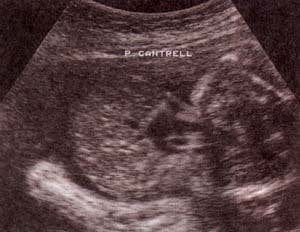

fig. 62. – (a). 18 semanas.corte sagital. |

fig. 62. – (b). corte transversal. estas formas de inicio precoz se hallan con frecuencia asociadas a anomalías cromosómicas. |